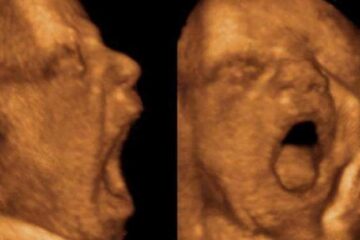

Chi sbadiglia molto nella pancia di mamma peserà un po’ di meno

Uno studio dell’università di Ferrara su Plos One ha analizzato 32 feti sani con ecografie 4D. Contribuendo al dibattito scientifico sulla grande domanda: a che cosa serve lo sbadiglio?